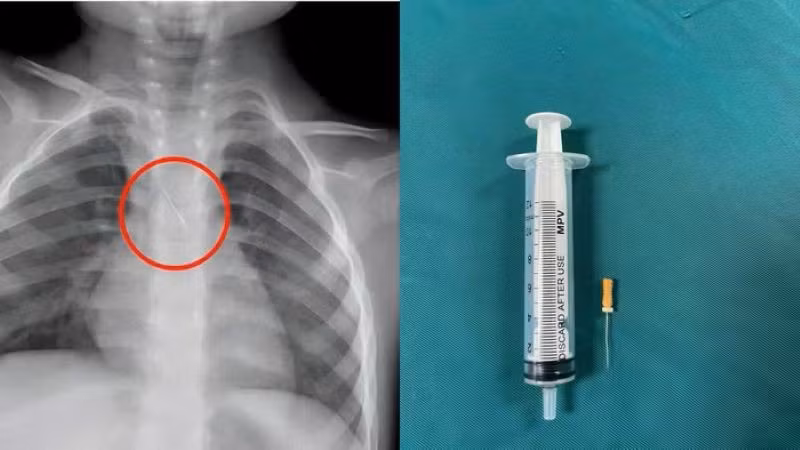

Dị vật trong đường thở của bệnh nhi. (Ảnh: Bệnh viện Đa khoa tỉnh Quảng Trị)

Trước đó, bệnh viện tiếp nhận bệnh nhi N.Q.T.Đ, 3 tuổi, trú tại xã Cửa Việt, Quảng Trị trong tình trạng ho nhiều, ho sặc. Kết quả chụp phim cho thấy 1 dị vật kim loại dài khoảng 22mm nằm ở góc carina (vị trí chia đôi khí quản) đe dọa gây tắc nghẽn đường thở.

Ngay lập tức, các bác sĩ hội chẩn liên khoa và quyết định nội soi phế quản cấp cứu. Dị vật được phát hiện có một đầu nhọn cắm vào 1/3 dưới khí quản, đầu còn lại nằm trong phế quản gốc trái.

Sau 15 phút thao tác khẩn trương, dị vật được kíp mổ lấy ra an toàn. Bé trai cải thiện triệu chứng ngay sau can thiệp và xuất viện sau 48 giờ theo dõi.

Theo gia đình bệnh nhi, khi đang được làm răng, kim chọc tủy bất ngờ rơi từ khoang miệng xuống đường thở của bé. Đây là trường hợp hy hữu có thể gây hậu quả rất nặng như xẹp phổi, viêm phổi, áp xe phổi, tràn khí màng phổi, thậm chí tử vong nếu không được xử trí kịp thời.